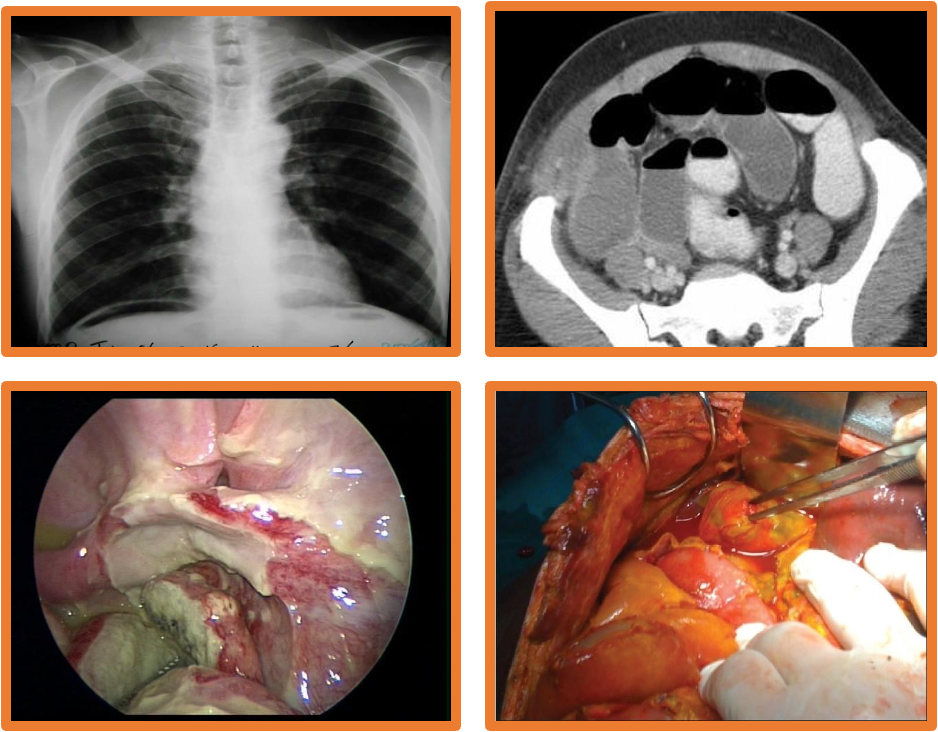

Investigations:

- Imaging: upright CXR, AXR, U/S, CT scan, peritoneal aspiration

- Operative management: Excision, repair, lavage & drainage